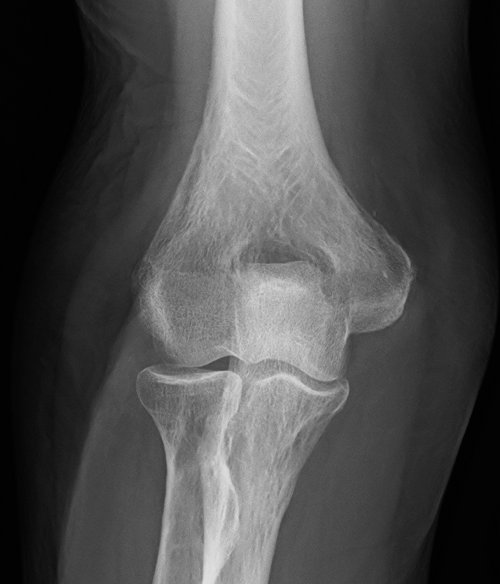

Behandlungsbeispiel

Die Orthovolttherapie ist eine schmerzfreie, nichtinvasive Behandlung mit speziellen energetischen Röntgenstrahlen.